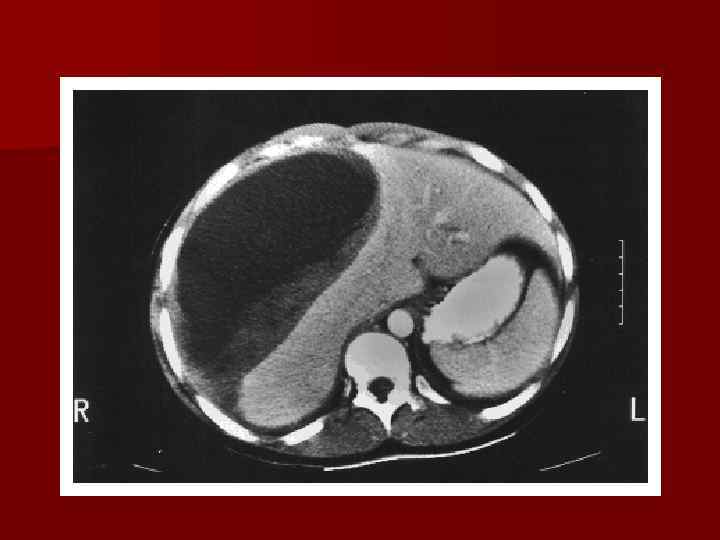

Патологическая анатомия Перипортальный и паренхиматозный некроз Отложение фибрина Гематома, повышение давления Разрыв капсулы печени

Патологическая анатомия Перипортальный и паренхиматозный некроз Отложение фибрина Гематома, повышение давления Разрыв капсулы печени

HELLP– синдром Посмертные изменения и данные биопсии печени • полисерозит и асцит • двухсторонний экссудативный плеврит • множественные петехиальные кровоизлияния в брюшину и в ткани поджелудочной железы • субкапсулярные гематомы и разрывы печени • перипортальный или очаговый паренхиматозный некроз печени • фибриновые микротромбы и отложения фибрина в синусоидах • вакуолизация и некроз гепатоцитов • тромбоцитарные микротромбы и множественные петехиальные кровоизлияния

HELLP– синдром Посмертные изменения и данные биопсии печени • полисерозит и асцит • двухсторонний экссудативный плеврит • множественные петехиальные кровоизлияния в брюшину и в ткани поджелудочной железы • субкапсулярные гематомы и разрывы печени • перипортальный или очаговый паренхиматозный некроз печени • фибриновые микротромбы и отложения фибрина в синусоидах • вакуолизация и некроз гепатоцитов • тромбоцитарные микротромбы и множественные петехиальные кровоизлияния